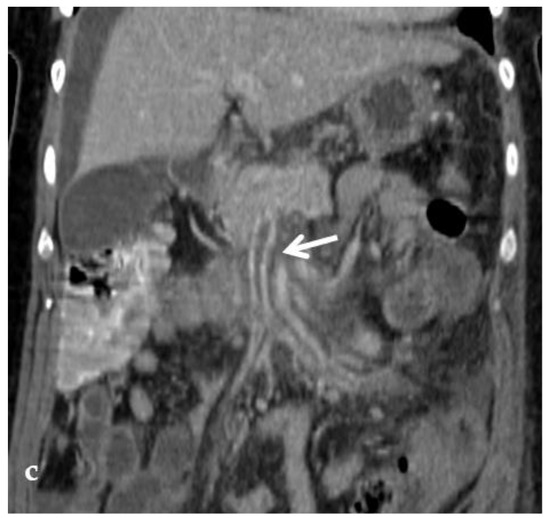

Conventional non-invasive imaging (CDUS, CT, MR) is not always reliable in assessing the patency of the native intrahepatic portal venous system and/or the Rex segment of the left portal vein in patients with cavernoma. At CDUS examination differentiating intrahepatic portal venous branches from venous collaterals in patients with the impaired portal venous flow can be challenging. Similar problems are faced by MR. One study compared MR and retrograde portography for the assessment of the Rex recess in children with extrahepatic PVT before Meso-Rex shunt surgery, demonstrating that only retrograde portography was reliable [63] (Figure 8).

Figure 8.

Right oblique anterior (30° cranial) view of a transjugular retrograde portography performed in a 9-year-old female with extrahepatic portal vein cavernoma due to a neonatal umbilical vein catheterization and portal vein thrombosis, who complained of symptoms of portal hypertension. She was a candidate for Meso-Rex bypass surgery. The image shows retrograde filling of the intrahepatic portal vessels with the complete visualization of the Rex segment (arrow) after wedged left hepatic venography. Meso-Rex bypass was then surgically performed.

Major concerns about transjugular retrograde portography in pediatric patients involve invasiveness, with radiation exposure and iodinated contrast agent administration [63].